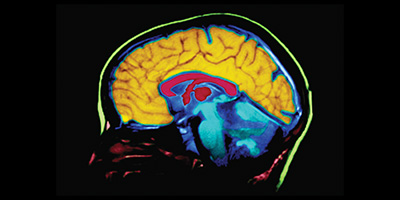

Al mismo tiempo, la inteligencia artificial se consolidó como una herramienta clave en el estudio del Alzheimer. Investigadores desarrollaron sistemas capaces de analizar imágenes cerebrales y reconocer patrones asociados a distintos tipos de demencia. Estas tecnologías permitieron acelerar la interpretación médica y aumentar la precisión diagnóstica, lo que facilita una atención más oportuna y decisiones clínicas mejor informadas.